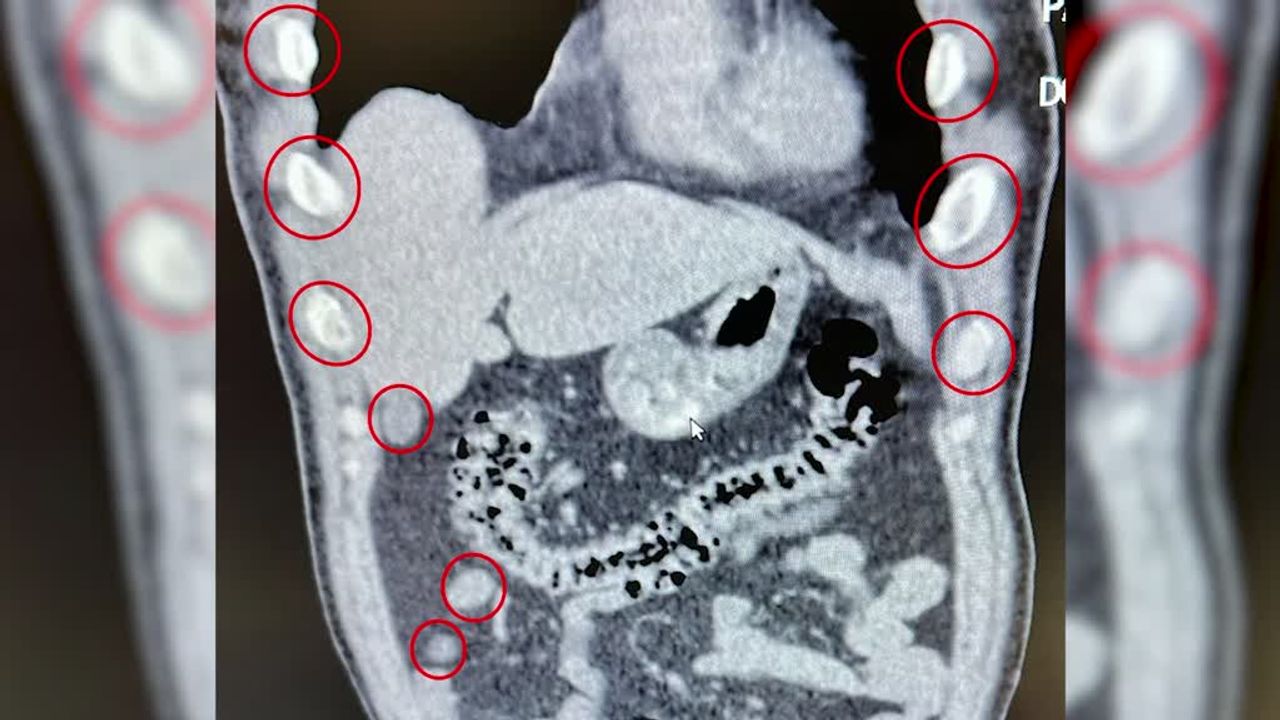

Bitlis Tatvan Devlet Hastanesine götürülen şüphelilerin röntgen ve tomografilerinde, mide ve bağırsaklarında çok sayıda yabancı cisim olduğu belirlendi.

Şüphelilerin yuttuğu 136 kapsüldeki 1 kilo 48 gram sentetik uyuşturucu, tıbbi müdahaleyle mide ve bağırsaklardan çıkarıldı.